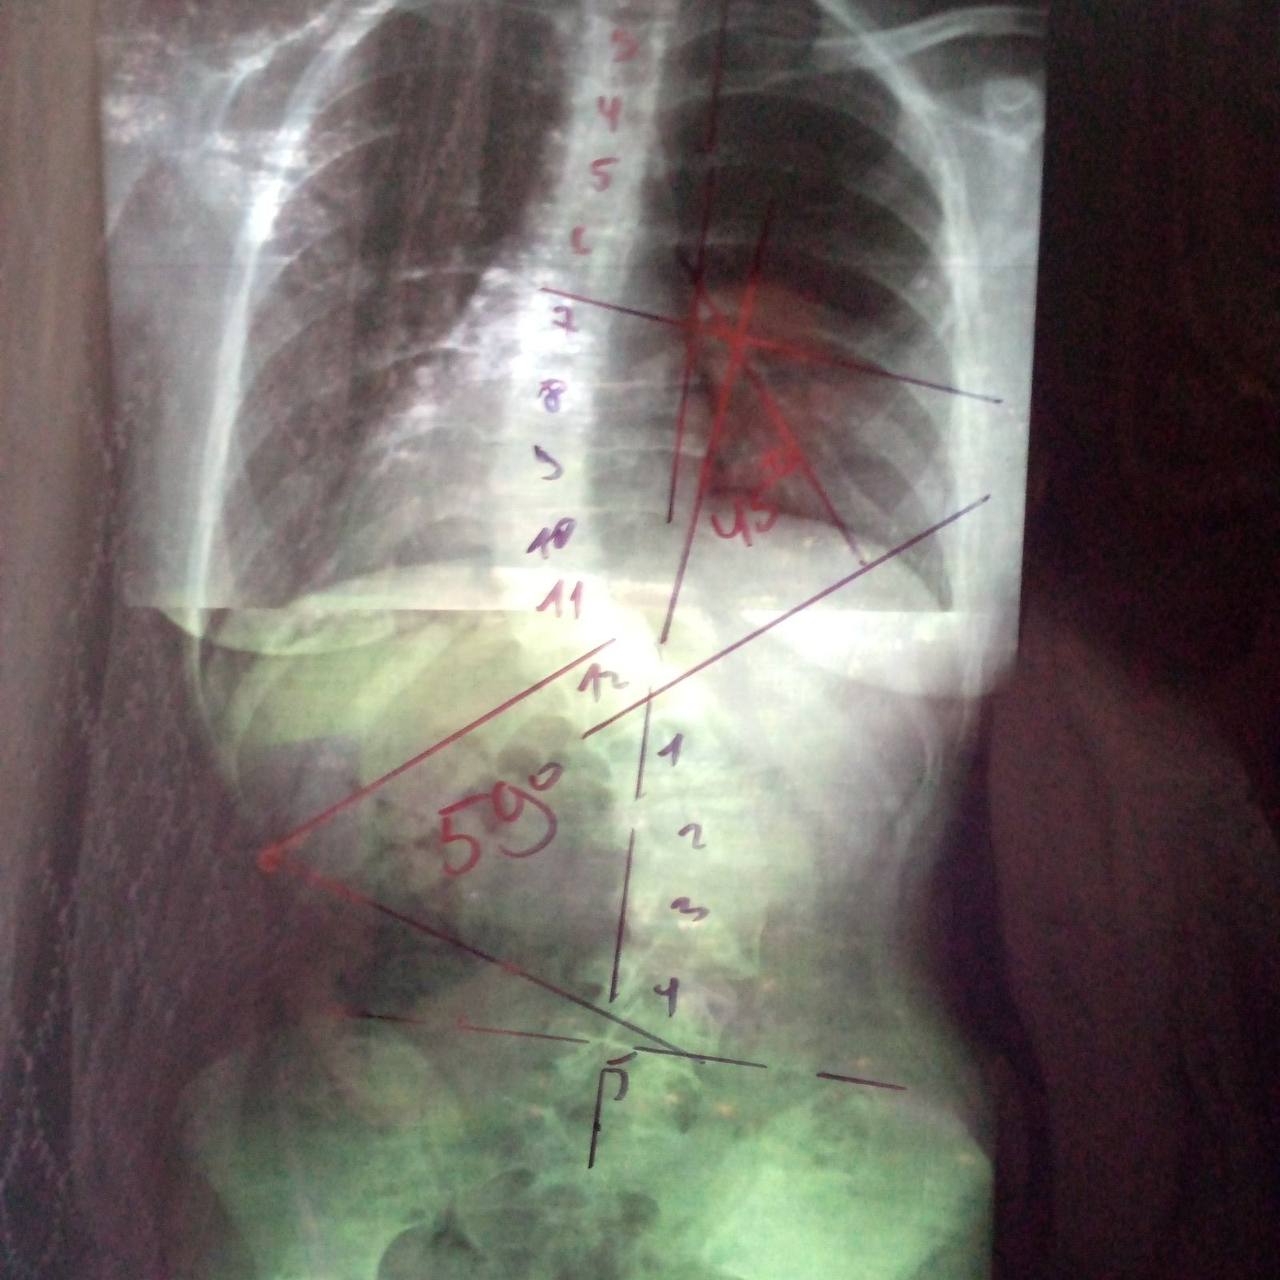

– У доньки S-подібний сколіоз. Кут основного поперекового викривлення – 59 градусів, кут грудного викривлення – 45 градусів. Нейрохірург повідомив, що донька має покази до хірургічної корекції деформації хребта. Як пояснили лікарі, у спину Ангеліни будуть вкручувати спеціальні металеві конструкції, що підтримуватимуть її поставу. Загалом, без цієї операції нам не обійтися, – наголошує мама дівчинки.